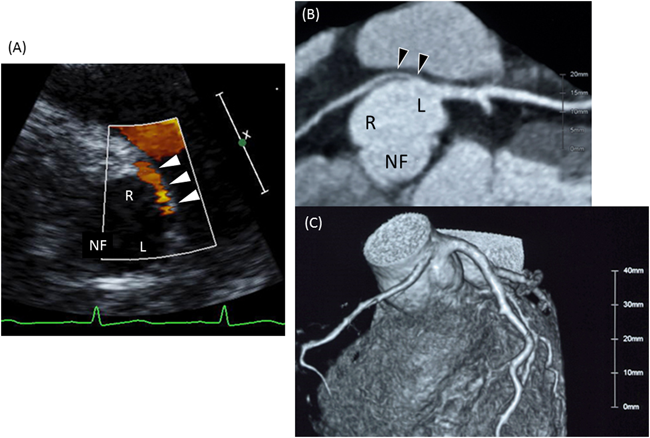

2) 左室冠動脈瘻(Left vetnriculocoronary arterial fistula: LVCAF)

剖検による報告では,左心低形成症候群の19%にLVCAFが認められる.このうちの97%は僧帽弁狭窄兼大動脈弁閉鎖の症例に合併しており,残りの3%が僧帽弁閉鎖兼大動脈弁閉鎖の症例に合併していた78).また,Boston小児病院からの剖検報告では,LVCAFは僧房弁狭窄兼大動脈弁閉鎖のみに認められ,このサブタイプの29%に認められた79).左室冠動脈瘻の発生機序は純系肺動脈閉鎖と同様に胎生期において左室内圧が高圧となることで類洞交通が残存する結果生じると考えられている.よって,高圧左室となりやすい僧帽弁狭窄兼大動脈弁閉鎖にLVCAFが多く合併する.また,僧帽弁狭窄兼大動脈弁閉鎖の左心低形成症候群の胎児に,卵円孔狭小ないしは早期閉鎖が合併する場合には,上昇した左房圧を駆動圧としてrestrictiveな左室へより多くの血液が押し込まれる血行動態となる結果,LVCAFの発達が助長され高度のLVCAFを形成すると考えられる80).また,非常に稀ではあるがLVCAFに冠動脈開口部閉鎖を合併する症例も報告されており,このような左室依存型冠循環症例では救命が非常に困難になると考えられる79)Fig. 12に左心低形成症候群(僧帽弁狭窄兼大動脈弁閉鎖)に卵円孔早期閉鎖と高度のLVCAFを合併した胎児例を示す.左室からLVCAFを介した血流が前下行枝を逆行して大動脈へ向かう所見を認める.

Pediatric Cardiology and Cardiac Surgery 32(2): 95-113 (2016)

Fig. 12 Left venrticulocoronry arterial fistula in hypoplastic left heart syndrome (fetal echo at 31 weeks)

(A): Early premature closure of the foramen ovale. Note the increased thickness of the atrial septum (arrow) and enlarged left atrium.(B): Retrograde flow (arrowhead) in the left anterior descending artery.(C): Retrograde flow in the left anterior descending artery confirmed by pulsed Doppler.AO: aorta; LA: left atrium; LAD: left anterior descending; LV: left ventricle; RA: right atrium; RV: right ventricle; PA: pulmonary artery.